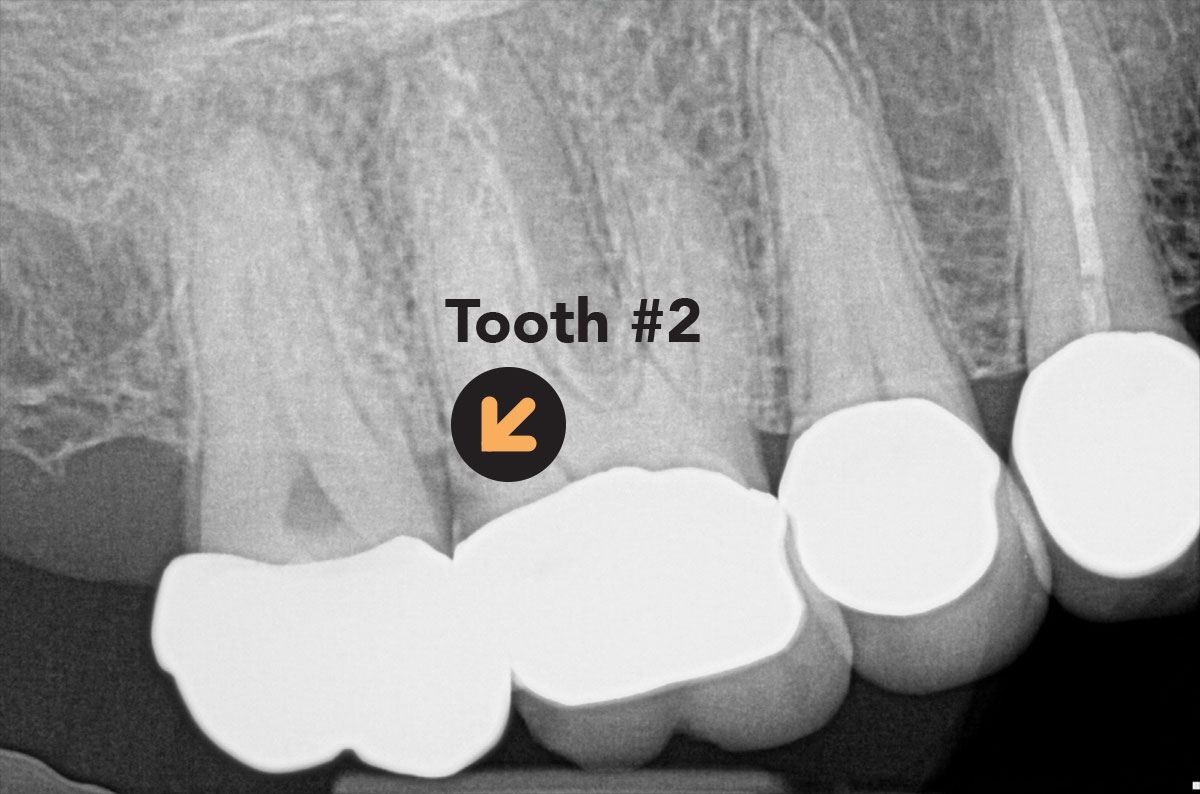

Image showing periapical radiograph of Tooth 2

Periapical radiograph of a symptomatic maxillary molar.